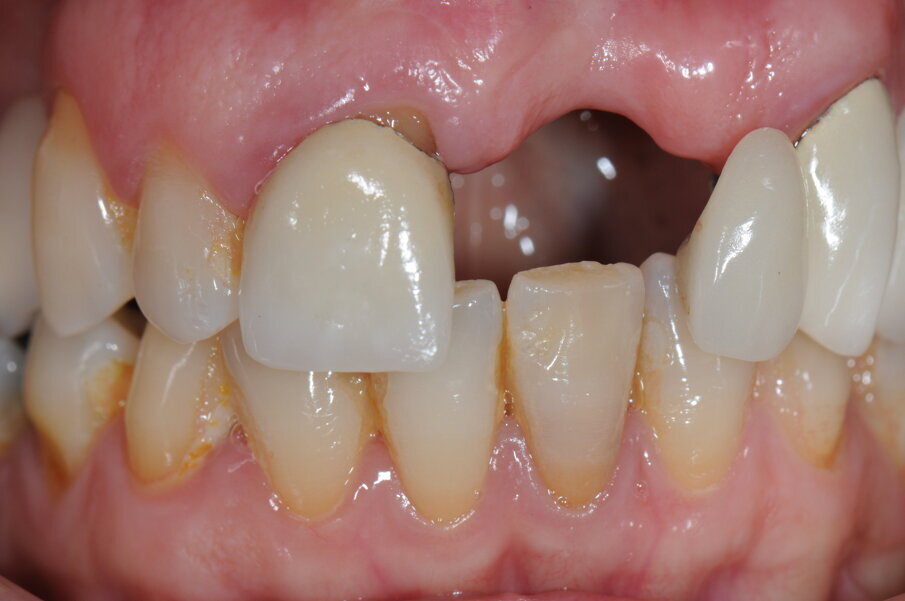

La paziente, donna, di anni 55, era giunta alla nostra osservazione richiedendo una riabilitazione protesica in area estetica a seguito di trauma provocato da un incidente stradale, avvenuto da circa 10 anni, che aveva determinando la perdita di due incisivi superiori in posizione 2.1, 2.2 (Figg. 1, 2).

Fig. 1 - Situazione iniziale della paziente al momento della prima visita.

Fig. 2 - Visione frontale della zona edentula.